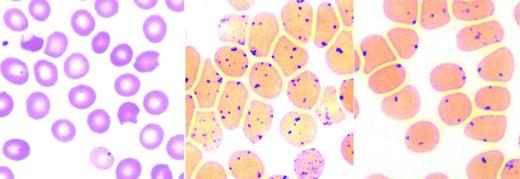

Beyond anemia, the reticulocyte count in HX patients is often increased to a level higher than that expected for the degree of anemia. Erythrocyte morphology on peripheral blood smear is relatively normal, with a few target cells, variable numbers of stomatocytes and dessicytes-contracted erythrocytes with their hemoglobin pooled to the side (Figure 4). The dehydration of HX erythrocytes is reflected by elevated MCHC and decreased osmotic fragility curve (increased osmotic resistance). These tests allow differentiation of HX from hereditary spherocytosis, where the MCHC is elevated, but osmotic fragility is usually increased. Despite cellular dehydration, HX patients exhibit mildly elevated MCV. This is attributed in part to an artifact of cellular stiffness. In electronic cell counters, the conversion of pulse height to cellular volume is dependent on cell shape. HX erythrocytes do not deform to the same degree as normal erythrocytes, causing the electronically measured MCV to be estimated ∼10% too high. Reticulocytosis also contributes to the elevated MCV.

Peripheral blood smears in altered volume homeostasis. (Left) Hereditary xerocytosis. (Right) Hereditary hydrocytosis. (Left) A Wright-stained peripheral blood smear from a patient with hereditary xerocytosis due to a PIEZO1 mutation showing rare stomatocytes, occasional dessicytes–dense, abnormal erythrocyte forms where hemoglobin appears puddled at the periphery, and rare target cells. (Right) A Wright-stained peripheral blood smear from a patient with hereditary hydrocytosis is shown. Numerous stomatocytes, erythrocytes with a central mouth-like “stoma” are seen.

The hereditary hydrocytosis syndromes, also known as hereditary stomatocytosis, are associated with elevated erythrocyte sodium concentration, reduced potassium concentration, and increased total sodium and potassium content.40 Excess cations elevate cell water leading to swollen, macrocytic, 110-150 fL, osmotically fragile erythrocytes with a low MCHC (24%-30%). Peripheral blood smear shows stomatocytosis (Figure 4). Missense mutations in the Rh-associated glycoprotein have been identified in a subset of hydrocytosis patients.26 Like the HX syndromes, splenectomy may be deleterious.39